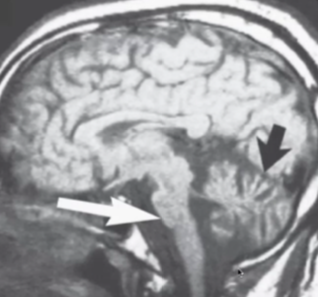

Características en RM de PSP

A

Atrofía mesencefálica (pinguino/colibrí en sagital)